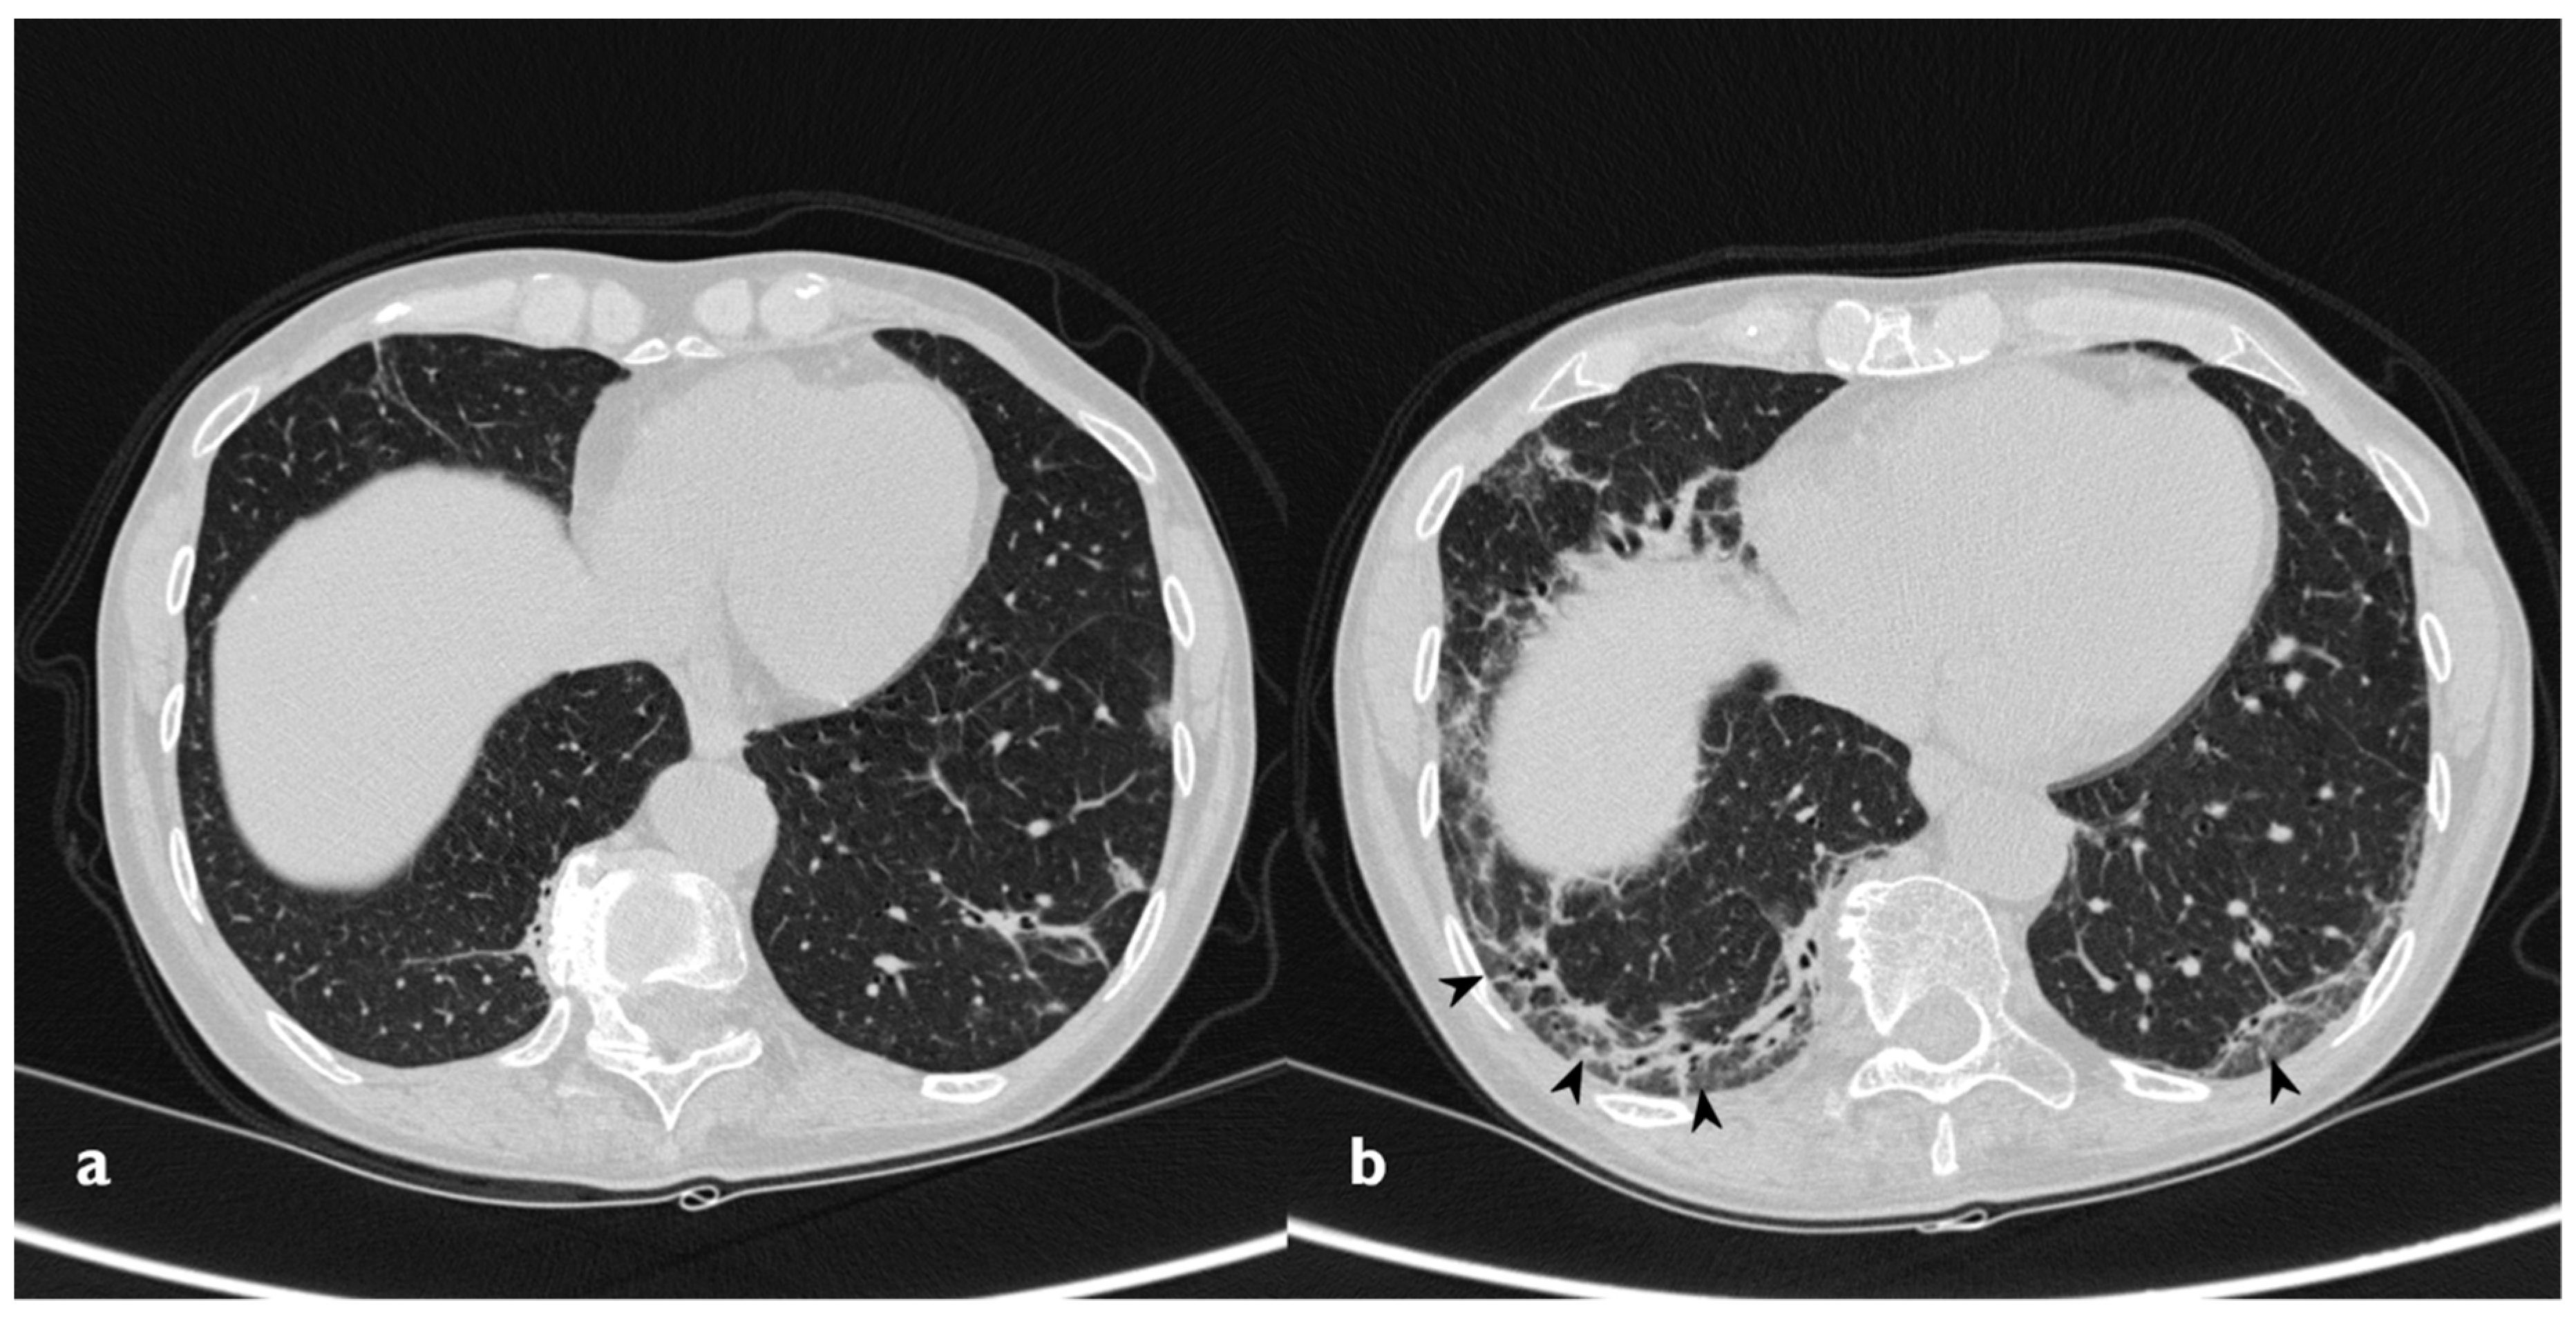

In 14 of the 18 patients who presented consolidations at the first CT scan, a complete resolution of these consolidations was observed (Figure 8); however, in three of them, new ones showed up in different pulmonary areas (migratory infiltrates) (Figure 9). In the other four patients with consolidations on initial CT images, two patients had a partial resolution, whereas the remaining two cases have shown no differences in consolidations at follow-up HRCT. The changing consolidations are summarized in Table 5.

Figure 8. On the left: baseline HRCT (a); subpleural consolidation in the right lower lobe. On the right (b): HRCT after 11 months of steroid therapy shows a disappearance of the consolidation.

Diagnostics 10 00262 g008

Figure 9. Migratory infiltrates. On the left (a): baseline HRCT; subpleural consolidation in the right lower lobe (white arrowhead). On the right (b): HRCT after 13 months of steroid therapy; the consolidations have disappeared in the first site, appearing in the left lower lobe (arrowhead).